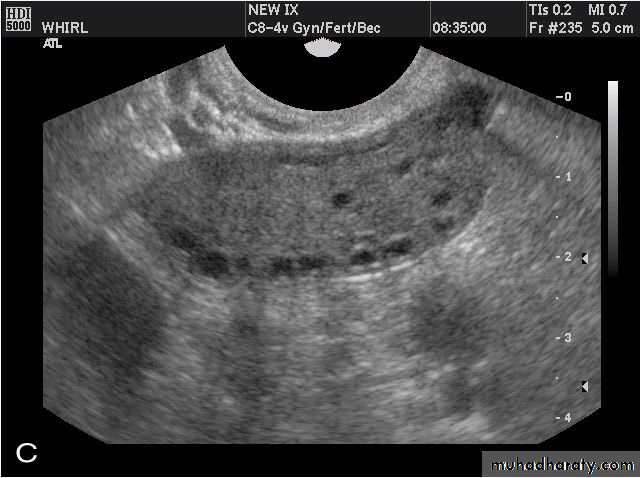

• Ovarian hyperstimulation syndrome (OHSS):

Transvaginal ultrasound images of ovarian hyperstimulation syndrome:

This young adult female patient showed multiple large theca lutein cysts of both ovaries, arranged in spoke-wheel pattern (ultrasound images above) which were the result of use of gonadotropins in the management of infertility. The cysts vary in size from 2 to 4 cms. with the ovaries massively enlarged (each ovary measures up to 7 cms. in size). This can be classified as grade-2 hyperstimulation of the ovaries (ovarian diameter from 5 to 10 cms.). There is not evidence of ascites. The color Doppler image of the ovaries shows vessels passing along the margins of the cysts. One of the complications of such enlarged ovaries in OHSS is torsion and in certain cases rupture of the ovaries, both of which are medical emergencies. Ovarian hyperstimulation syndrome is known to occur more frequently in patients of pre-existing Polycystic ovaries (PCO).